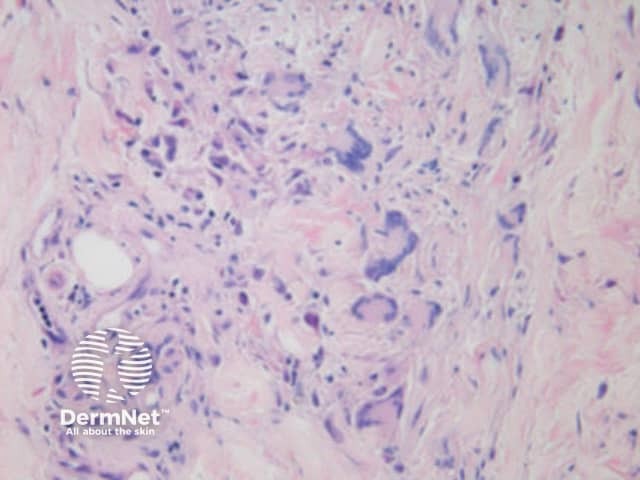

Skin biopsy of the lesion is performed. The histopathological finding of non-caseating granulomas similar to those found in intestinal Crohn disease supports the diagnosis of Crohn skin disease. In patients with no intestinal disease whose skin biopsy shows non-caseating granulomas, a thorough gastrointestinal history and systemic work-up should be performed.

Histology of cutaneous granuloma due to Crohn disease, New Zealand Medical Journal. 2006